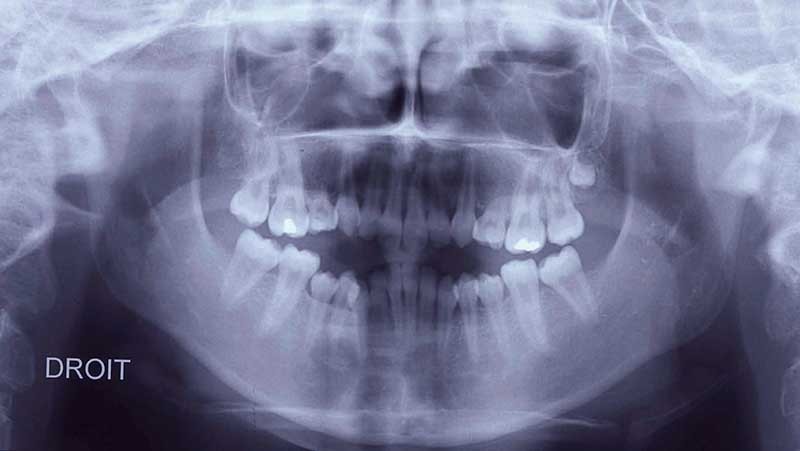

Pour les raisons précitées, les traitements orthodontiques menés en collaboration avec un chirurgien maxillo-facial sont de plus en plus fréquents [7]. Dans le cas clinique qui illustre cet article, il s’agit d’une jeune fille âgée de 13 ans lors la première consultation (fig. 1, 2, 3).

Sur le plan squelettique, elle présente une classe 3 par rétromaxillie dans un profil cisfrontal associé à une hyperdivergence faciale. La proalvéolie incisive maxillaire et la forte rétroalvéolie incisive mandibulaire singularisent le secteur alvéolo-dentaire (fig. 4 et 5).